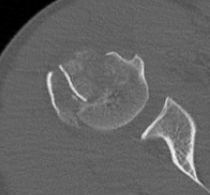

Four part